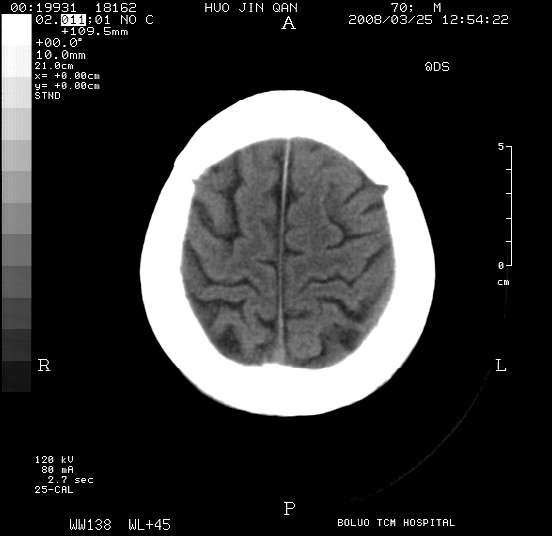

以下是引用随光逐影在2008-3-25 20:15:00的发言:[br]双侧额颞顶部亚急性(或慢性)硬膜下血肿。

以下是引用liuyue在2008-3-26 18:57:00的发言:[br]以下是引用随光逐影在2008-3-25 20:15:00的发言:[br]双侧额颞顶部亚急性(或慢性)硬膜下血肿。 [br]支持![br]可以无明显外伤病史,老年人可以在激烈摇晃或轻微头部碰创头部时,发生硬膜下出血.